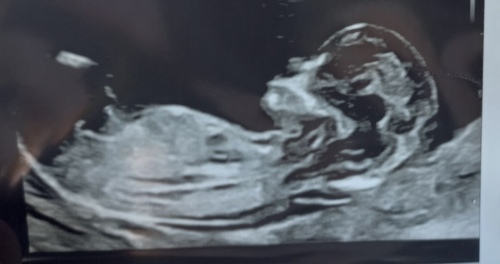

https://community.24baby.nl/forum/zwanger/het-grote-nub-topic-deel-27-YzZwkZ